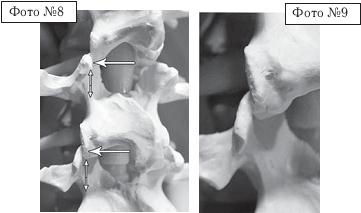

На фото № 8 макета позвоночника наблюдается перерастяжение дугоотростчатых суставов вследствие вытяжения.

На фото № 9 наблюдается перерастяжение дугоотростчатого сустава (увеличенный вариант).